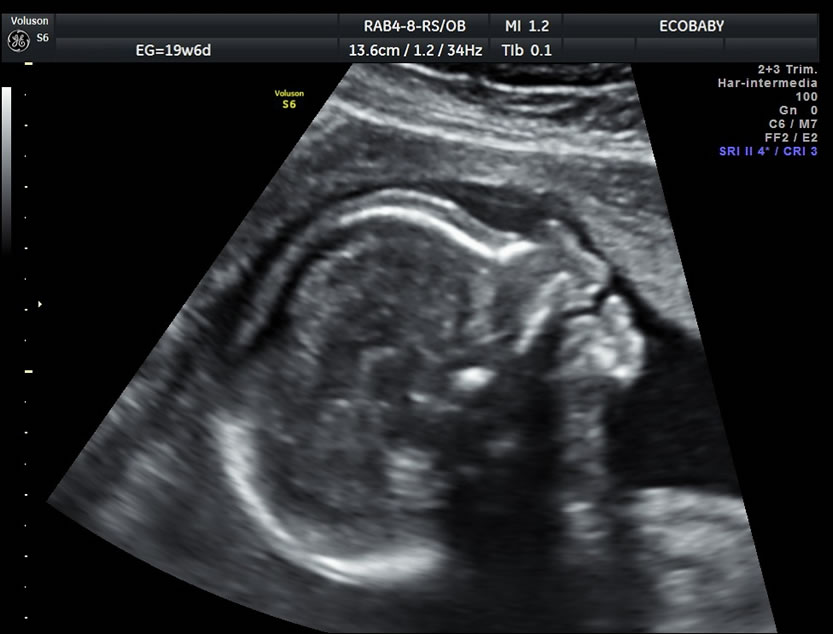

Cerebro, cuello, cara, tórax, corazón (diferentes cortes que muestran las cavidades y la correcta entrada y salida de arterias y venas), abdomen (normalidad de la pared, estómago, intestino, riñones, vejiga), miembros inferiores y superiores y columna vertebral.